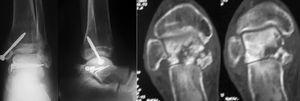

El seguimiento a la largo plazo de las fracturas del astrágalo identifica que la causa más común de los resultados pobres está asociada con la OA subastragalina, tibioastragalina y talonavicular, tanto en nuestra revisión, que alcanzó al 21% (8) de los casos (figs. 9 y 10), como en otros trabajos revisados15,17,19,22,23.

Fig. 9. --A) Fractura del cuerpo del astrágalo tipo B más rotura completa de los 3 ligamentos laterales del tobillo. B) Abordaje bilateral. Osteosíntesis. Sutura de ligamentos. Radiografía y tomografía computarizada a los 18 meses. Artrosis subastragalina y tibioastragalina.

Fig. 9. --a: Type B fracture of the astragalus with complete rupture of the 3 lateral ankle ligaments. b: Bilateral approach. Osteosynthesis. Ligament suture. Radiography and CT at 18 months. Sub-astragalar and tibio-astragalar arthrosis.

Fig.10. --Resultado a los 32 meses. 50° de BA. NAV del cuerpo y artrosis subastragalina y tibioastragalina

Fig.10. --Results at 32 months. BA 50º. Avascular necrosis of the astragalus and sub-astragalar and tibio-astragalar arthrosis.